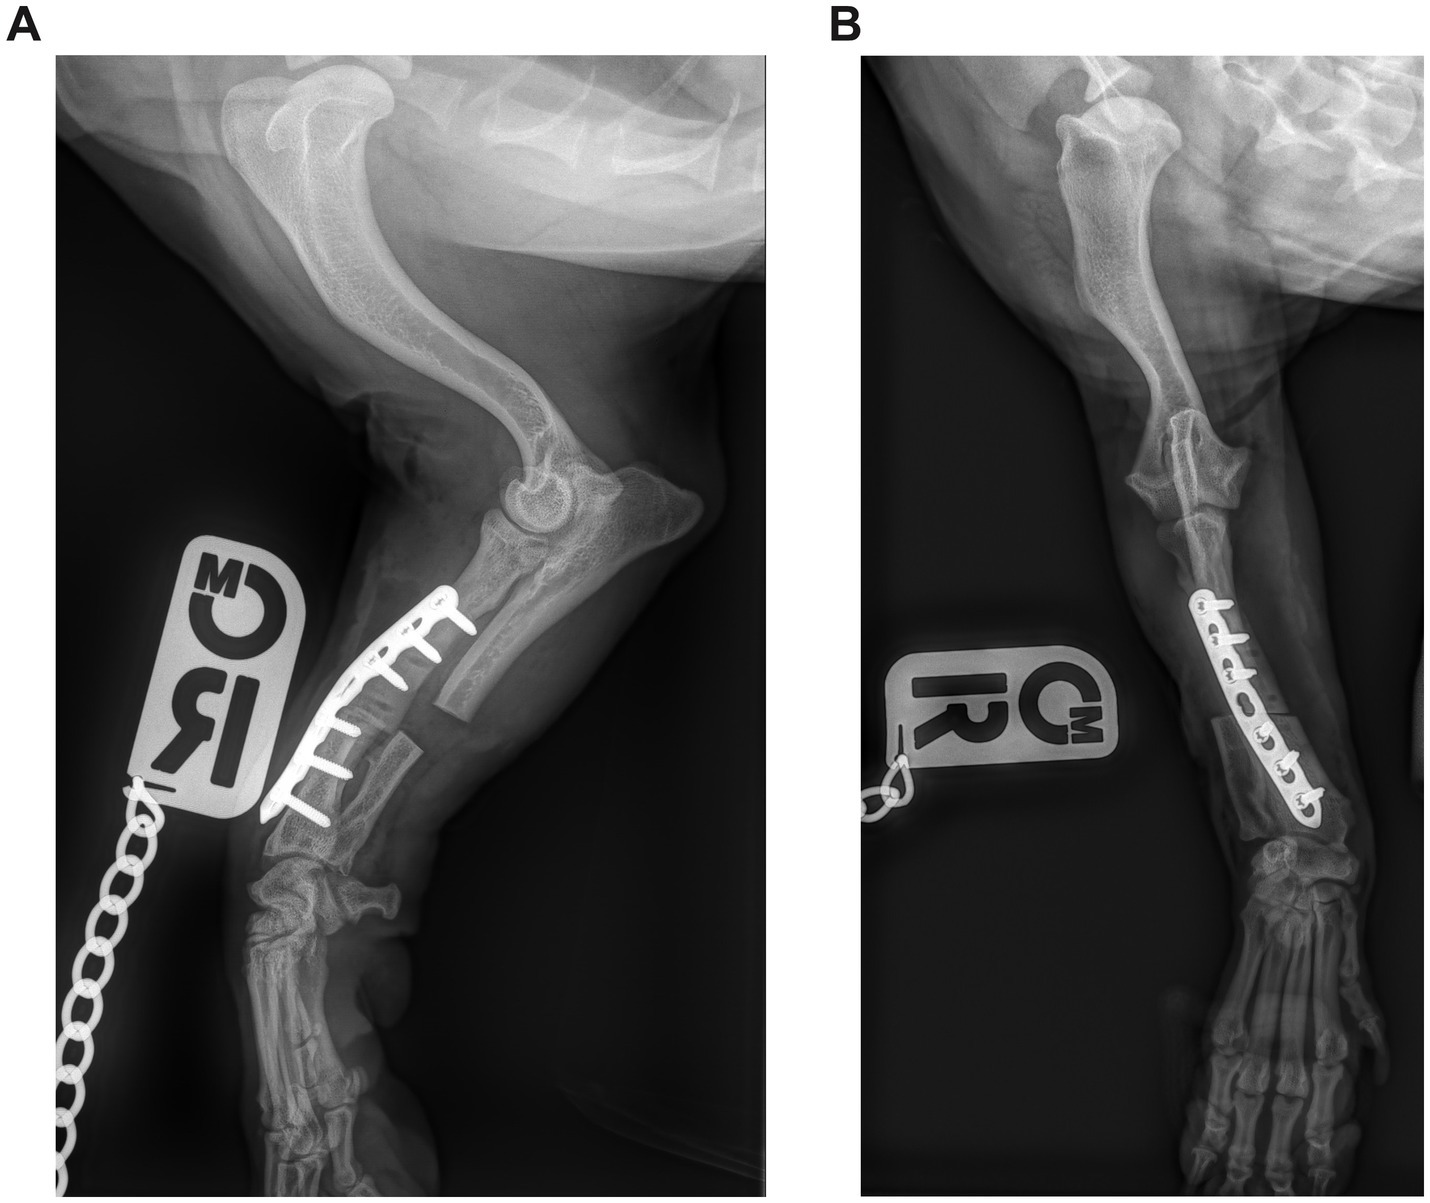

Immediately after surgery, the axial and rotational alignment of the antebrachium was grossly inspected, and orthogonal radiographs were performed to assess the adjacent joints’ orientation and implant position (Figures 3, 4). No objective measurements of antebrachial alignment were recorded. A light bandage was applied to the limb just distal to the elbow to control soft tissue swelling for 24 h. All patients were hospitalized for at least 24 h and received methadone analgesia based on the Short Form of the Glasgow Composite Measure Pain Scale (0.1–0.2 mg/kg every 2–4 h if the score was 6/24 or above).

Figure 3. (A) Postoperative mediolateral and (B) craniocaudal radiographs of the antebrachium of the dog from Figure 1. The ostectomy has been fixed with a single Locking Compression Plate.